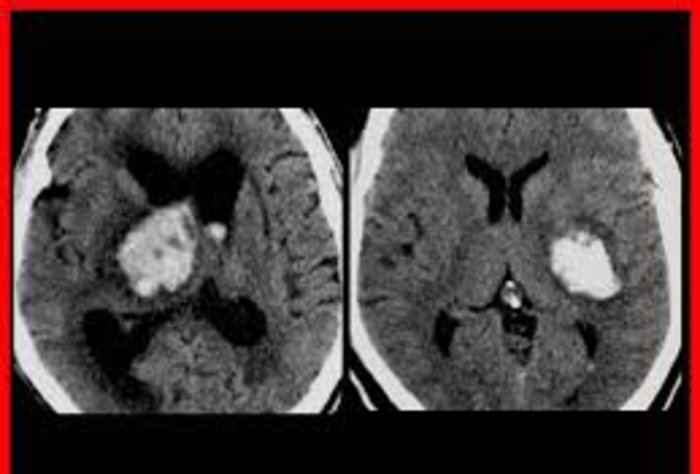

Manejo del ACV en la Emergencia

El ataque cerebreovascular se define como la presencia de signos clínicos que se desarrollan en forma súbita o rápida y responden a una alteración focal de la función cerebral de origen vascular

La Jornada de Actualización en ACV Isquémico cumplió con el objetivo de informar y capacitar a los profesionales médicos y personal de salud en el manejo de pacientes que padecen un infarto cerebral

Uruguay registra un elevado número de casos de accidentes cerebrovasculares (AVC). La inmediatez en la asistencia es determinante para poder salvar la vida